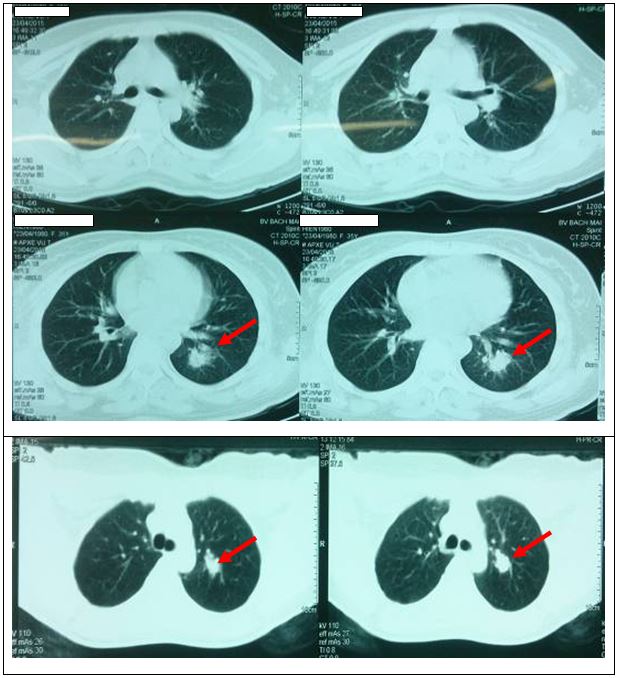

Chụp cắt lớp vi tính lồng ngực: Tổn thương dạng khối thùy trên phổi trái kích thước 1 x 2 cm và tổn thương thùy dưới phổi trái kích thước 0,5 x 0,7 cm.

Hình 2: Hình ảnh chụp cắt lớp vi tính lồng ngực: Tổn thương dạng khối thùy trên phổi trái kích thước 1 x 2 cm, tổn thương thùy dưới phổi trái kích thước 0,5 x 0,7 cm.